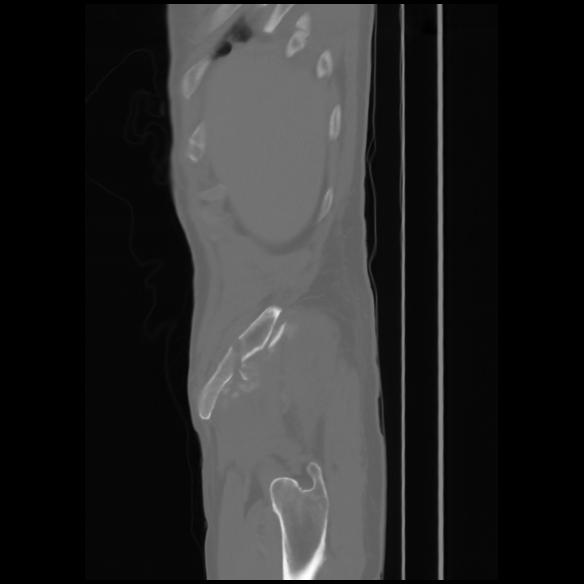

7 CUERPO,CE,Sagittal,3.000,CUERPO,Sagittal,